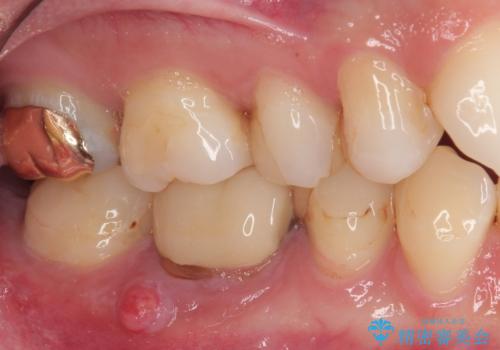

- 左右ともに下顎の奥歯に違和感や痛みを感じるとのことで来院された患者様です。

左下奥歯は詰め物と周辺の歯が欠けて、しみている状態でした。

部分的な詰め物ですと、再度破損リスクが高いため、高強度のセラミッククラウンにて補綴治療を行うこととしました。

また、親知らずが埋もれており、よい機会なので抜歯を行ってからセラミッククラウンを装着することとしました。